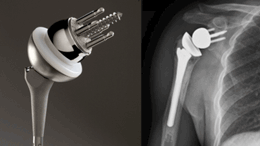

역행성인공관절치환술

• 그림